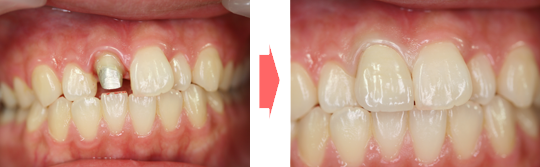

オールセラミック クラウン

口腔内のすべての歯に適用できる方法で、土台となる歯の外側に人工歯としてすっぽりかぶせるタイプです。

セラミックのみで作られているので金属アレルギーの方に有効ではないでしょうか。

インプラントとの併用で天然歯とほとんど見分けがつかない仕上がりが期待できます。